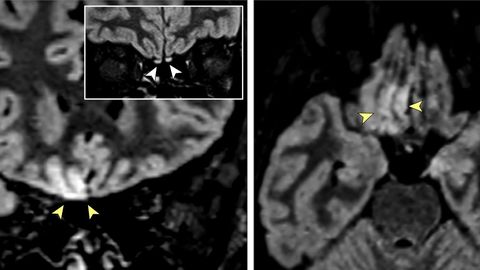

Imágenes obtenidas por resonancia magnética en las que los especialistas señalan alteraciones en la zona del cerebro asociada a la percepción del olfato

Imágenes obtenidas por resonancia magnética en las que los especialistas señalan alteraciones en la zona del cerebro asociada a la percepción del olfato JAMA